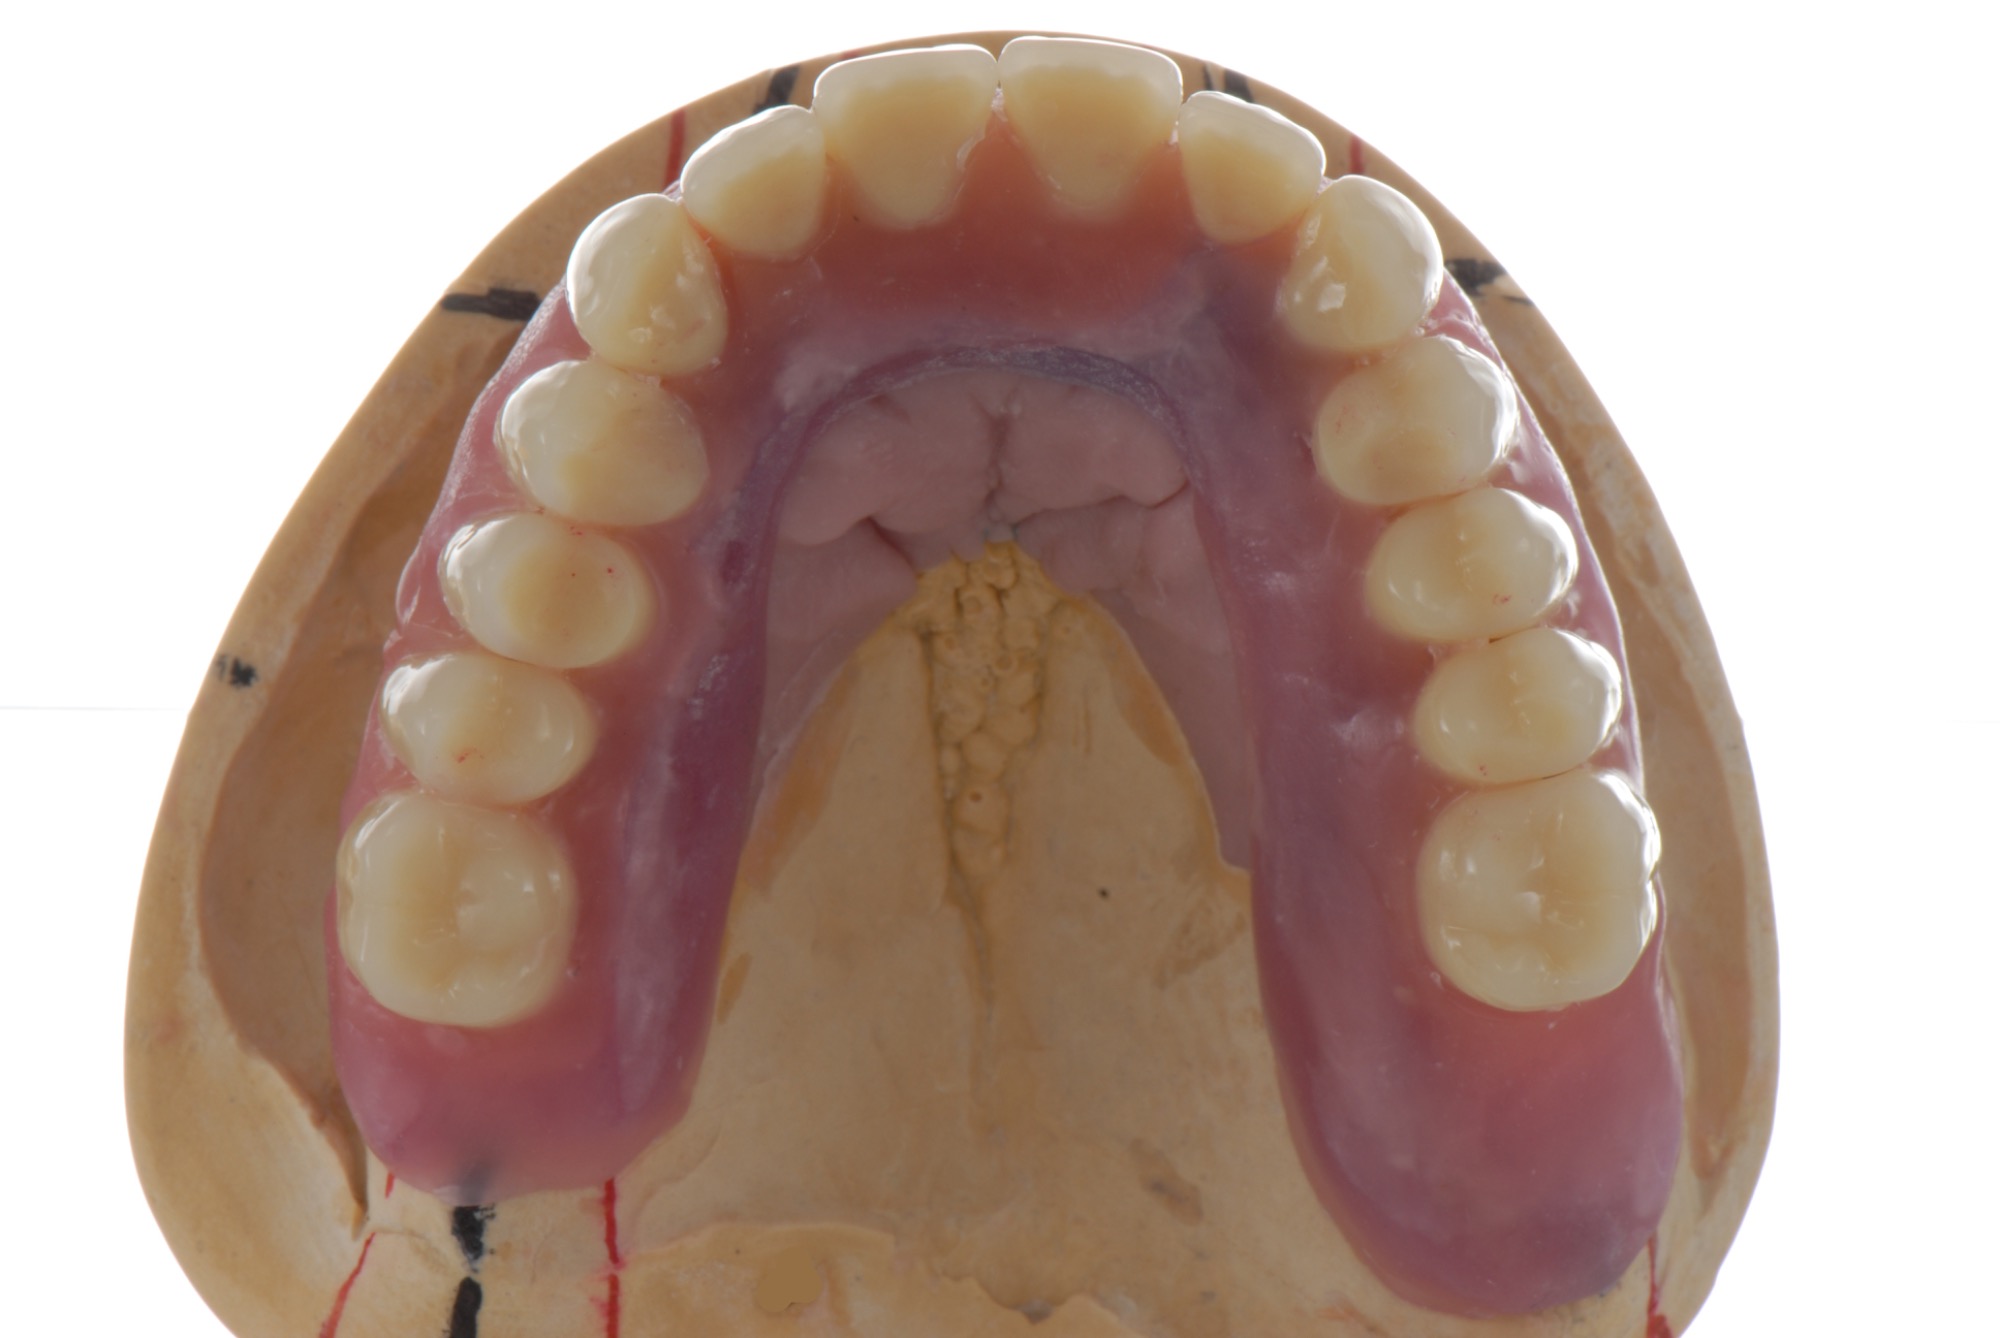

Teleskopierende Oberkieferbrücke. Wie die eigenen Zähne, aber einfach zu reinigen.

Teleskopierende Brücken im digitalen Ablauf hergestellt.